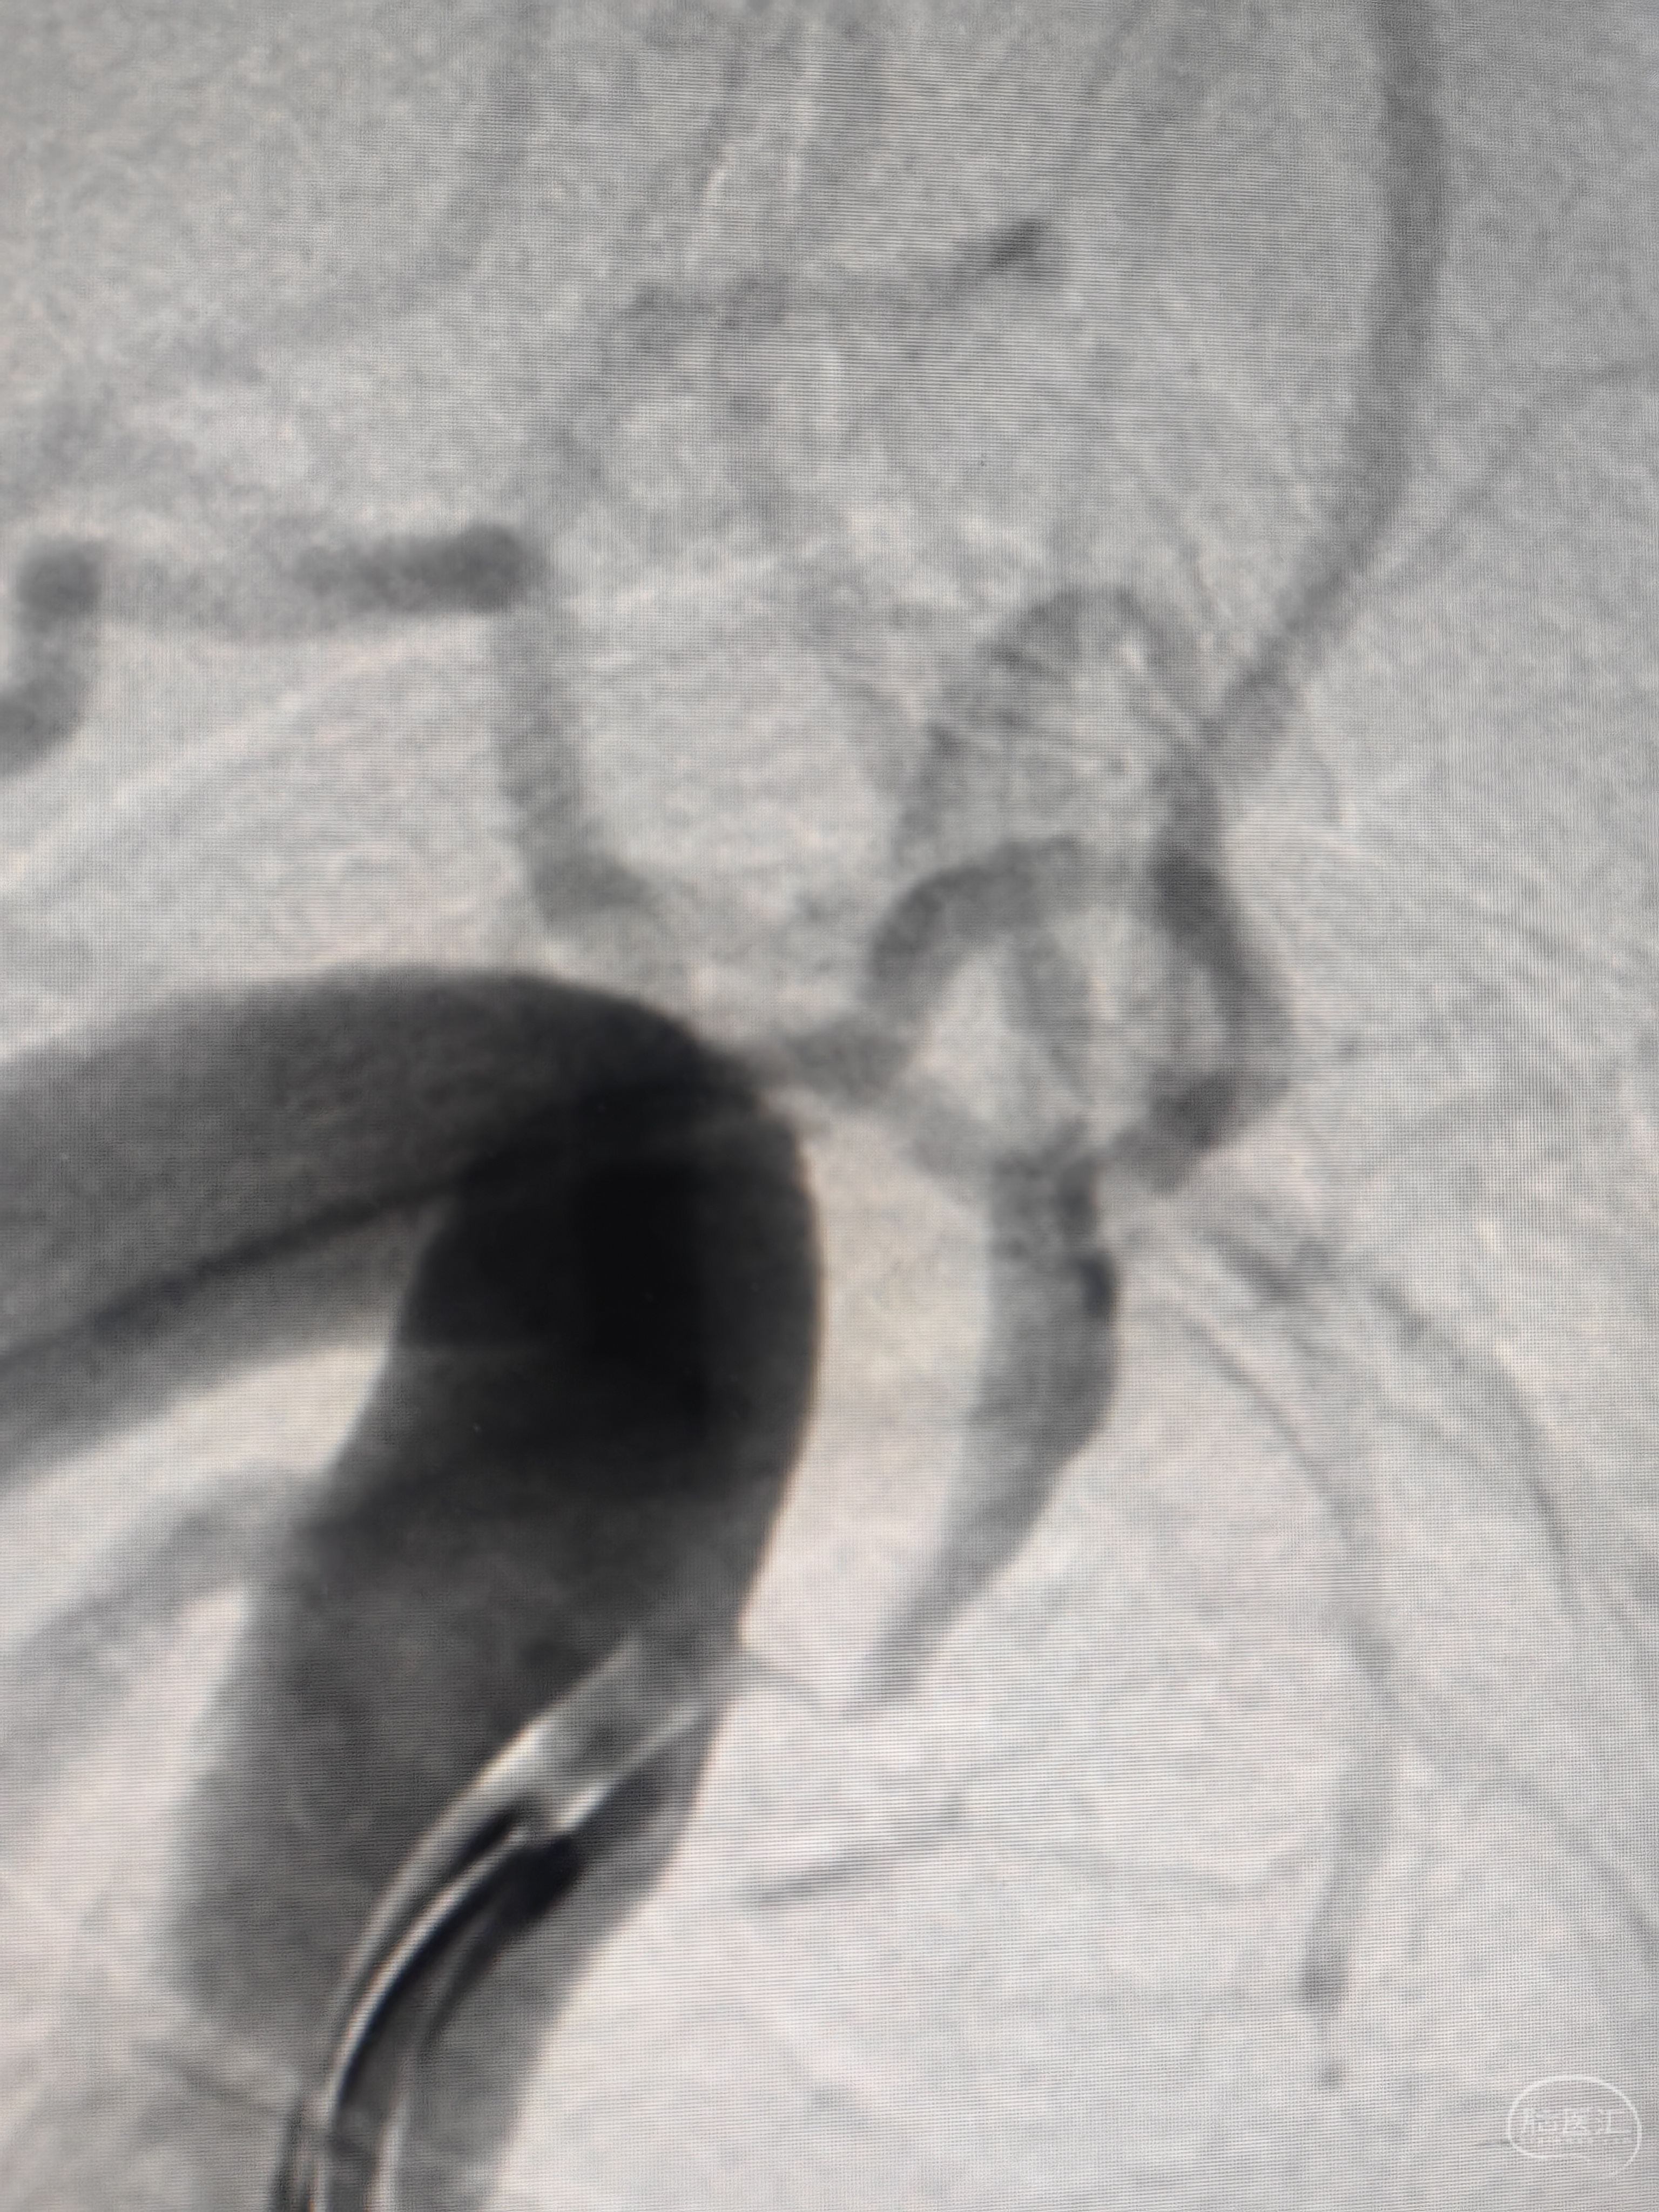

上SL-10微导管不行,加125管改变角度还是不行,此处省略长时间,最后的最后,想到用猪尾管切一半来提供角度便于支撑,but,猪尾长度110,guiding长度100,加个y阀无法出头,取了y阀裸上,不能路途不能造影,大概预估的角度上

通过的一瞬间,甚至都是有多巴胺分泌的了,可以想象过程有多坎坷😂